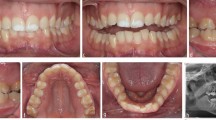

Since the jaw and dentition of early orthodontic patients are still in a dynamic development, and the dento-maxillofacial growth and development vary among different patients, an unerupted tooth is an impacted tooth or not needs to be carefully diagnosed. Some teeth may be diagnosed as impacted teeth (Fig. 4c), while others may only be identified as having impaction tendency (Fig. 4d–f).

Congenital Missing Teeth